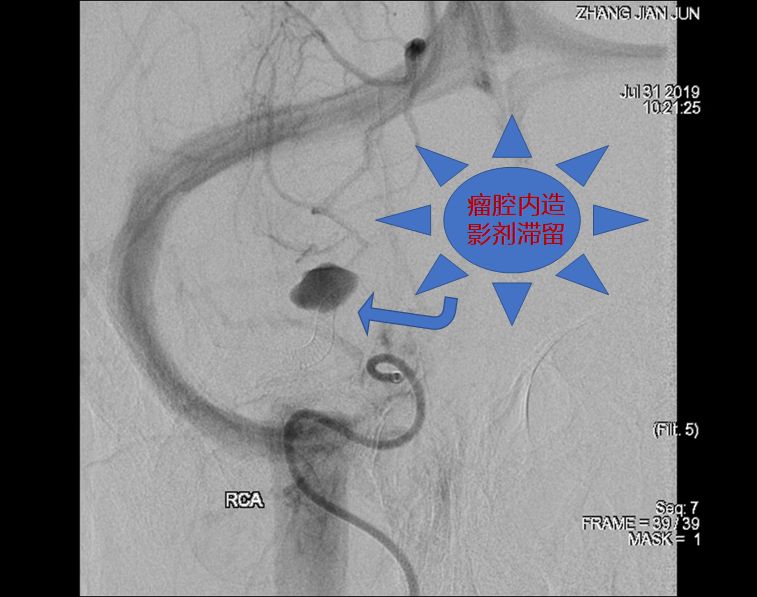

2、术后18小时急诊DSA(图六)。

治疗颅内动脉瘤新型密网支架,pipeline治疗椎动脉夹层动脉瘤

图六

此患者为一53岁的男性患者,因发现右侧大脑中动脉M1段动脉瘤2周而住院治疗。从患者影像学资料分析,患者动脉瘤的形态学很不稳定,而且有明显增大的趋势,血流滞留很明显,考虑夹层动脉瘤可能性较大。患者有头痛的病史,对比两周前的影像资料,动脉瘤有增大趋势。患者治疗意愿比较强烈。造影结果显示,患者夹层动脉瘤上方有一较大的分支动脉—豆纹动脉。请神经外科会诊,会诊意见:手术干预难以保留豆纹动脉,开颅手术不具有治疗优势。与患者及患者家属沟通后,患者及患者家属积极要求介入治疗。

术前讨论:如何使患者获得最大受益?因为是夹层动脉瘤,如果填圈治疗,一是外侧豆纹动脉会即刻闭塞,更易引起临床症状;二是填圈治疗有使夹层动脉瘤撕开、出血的风险。所以经讨论我们决定采取一种折中方案,只放密网支架而不填圈的手术方式。我们希望通过密网支架的支撑,使夹层动脉瘤慢慢消失。通过慢性闭塞,给夹层动脉瘤上方的豆纹动脉部位一个代偿血管增生的时间,减少患者发生偏瘫的概率。经过精准测量后,选择合适支架。术中手术顺利,术后进行血管三维重建,密网支架放置良好,贴壁良好,可以清晰的看到豆纹动脉。术后患者回到病房后,一般情况良好。术后18小时后患者出现言语含糊、左侧中枢性面舌瘫,左侧肢体偏瘫,CT排查出血后考虑是患者夹层动脉瘤上方的豆纹动脉闭塞引起的症状。立即行全脑血管造影,发现豆纹动脉确实消失。确定豆纹动脉消失是引起患者临床症状的一个主要原因。这是天坛医院第一例在密网支架植入术后第一天就复查造影的患者。造影结果让我们惊喜的发现,密网支架治疗后,不到18个小时,患者的动脉瘤几乎完全消失。从而证明,我们的手术通过精准测量,选择合适的密网支架对夹层动脉瘤的治疗效果以及夹层的修复效果是非常明显的。当然,患者出现穿支动脉的闭塞,是我们术前充分考虑的,且无法避免的一个并发症。术后给予神经康复,高压氧治疗,患者有明显的好转趋势。我们希望通过后续的康复治疗可以使患者的生活接近正常,同时我们也在密切随访患者,希望患者动脉瘤完全消失,并且正常生活。